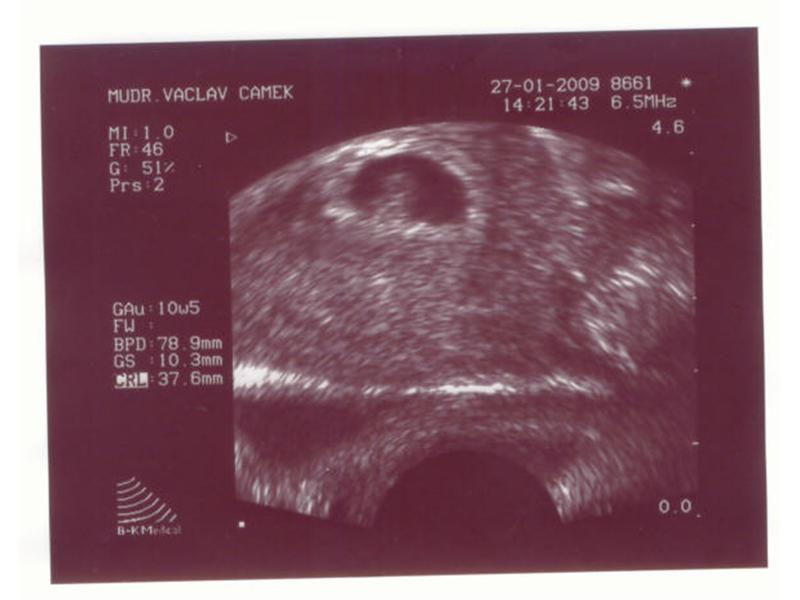

Zdroj: archiv redakce